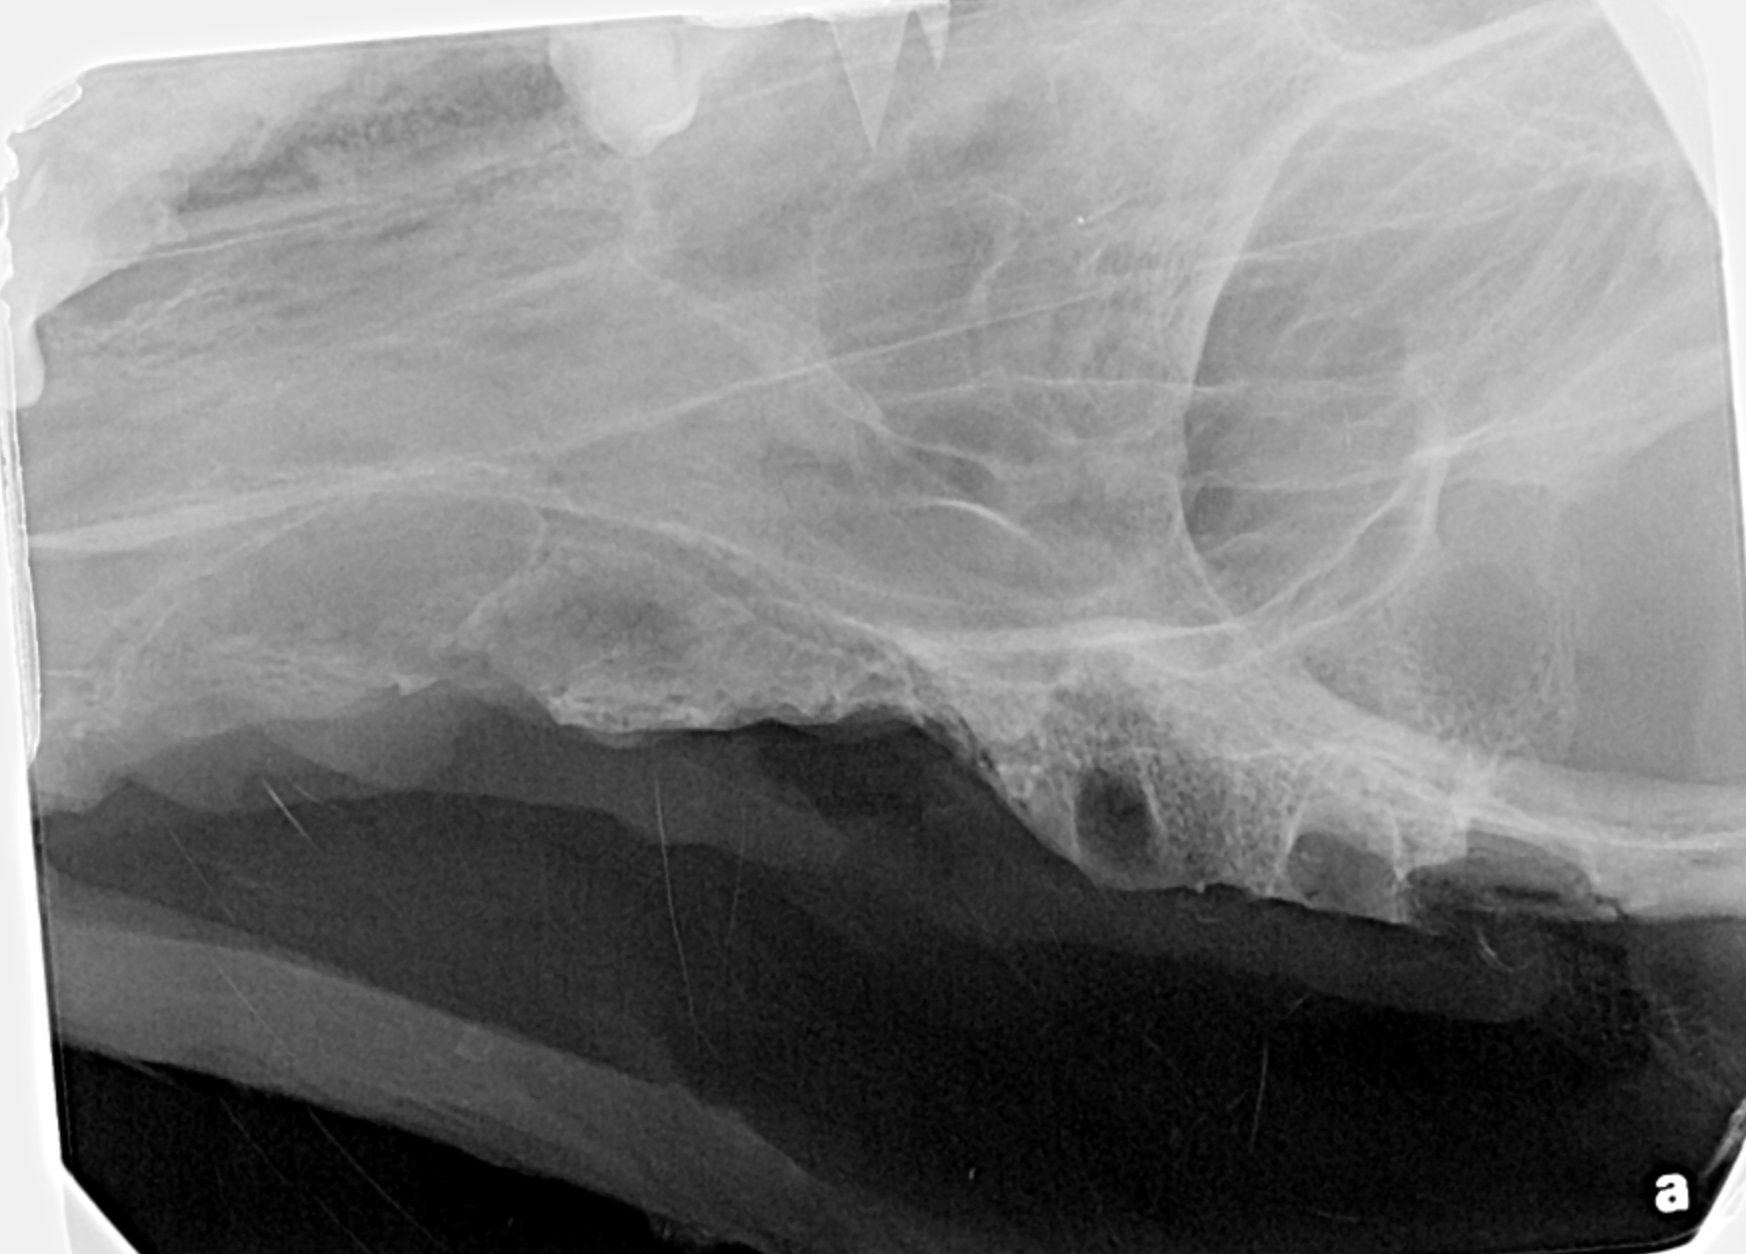

Advanced Oral Surgery

Major and advanced oral surgery such as cleft palate surgery, jaw fracture repair and oral tumor removal.